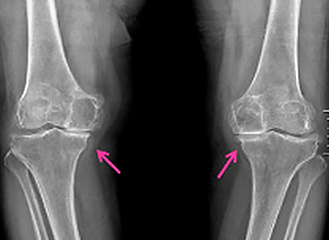

무릎의 연골이 닳아 없어져 염증과 통증이 발생하는 관절질환

관절염은 나이가 들어감에 따라 연골이 닯아 없어지거나, 선천적으로 관절이 비정상적인 경우, 비만이나 과도한 운동 등으로 관절에 무리가 와서 생기는 등 원인이 다양합니다. 관절염이 발생함에 따라 관절이 뻣뻣해지거나 관절이 압박당하는 느낌이 들고, 부종 등의 증상이 나타나며 걸을 때 통증이 더욱 심해지고 가만히 쉴 때도 증상이 나타날 수 있습니다.

관절은 연골, 활액낭, 인대, 힘줄, 점액낭, 근육 등으로 구분할 수 있는데, 그중에 하나 이상에 문제가 생겨 발생하는 질병이 관절염입니다.